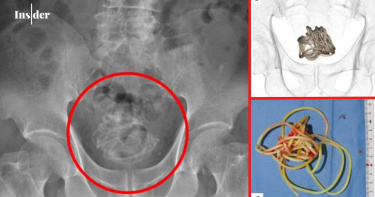

吃下沒煮熟豬肉!他一照「體內全是蟲」 醫示警:爬進腦就得動手術

豬肉務必煮熟再吃!美國佛州大學急診科醫師加利(Sam Ghali)日前分享一張CT掃描照片,只見這張圖上,布滿了白色如同米粒般的異物,係因這名患者吃下沒煮熟的豬肉,感染了「囊蟲病」(cysticercosis)。根據外媒《每日郵報》(Daily Mail)報導,加利解釋,囊蟲病是由「豬肉絛蟲」引起,蟲卵會隱藏在未煮熟的豬肉裡,一旦被人類吃下肚,就會在腸道中孵化成幼蟲,而幼蟲會鑽過腸壁、進入血液,擴散到全身各處。不過,牠們在被人體免疫系統殺死後,會形成堅硬的鈣化囊腫,在CT掃描圖上,就會呈現出白色橢圓形的「米粒」。加利進一步說明,除了吃下未煮熟的豬肉外,這些蟲卵也可能因糞口傳染染疫,這種傳播方式主要因感染者在上廁所後沒有正確洗手而發生,或者蟲卵透過人體排出後,汙染水源而致。報導指出,如果鈣化囊腫進入大腦,將會引起頭痛甚至癲癇發作,也可能讓人出現意識混亂、頭暈、腦積水等病症,在這樣的情況下,通常需要手術進行切除;若囊腫到達眼睛,恐怕會使人視力模糊,造成其他感染問題。對此,加利也強調,囊蟲病的預後情況通常很好,但不幸的是,仍有一些病例將會致命,據估計,全球每年約有5000萬人感染,導致約5萬人死亡,「所以應該盡力保持清潔、經常洗手,永遠不要吃生的或未煮熟的豬肉」。